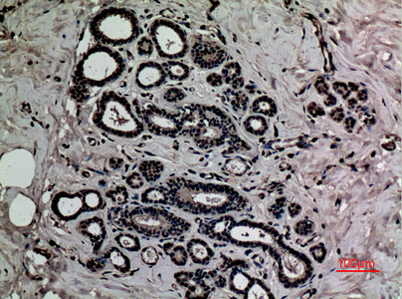

Product name: HMG-1 (Acetyl Lys12) rabbit pAb

Dilutions: Western Blot: 1/500 - 1/2000. IHC-p: 1:100-300 ELISA: 1/10000. Not yet tested in other applications.

Immunogen: Synthesized acetyl-peptide derived from the N-terminal region of human HMG-1 around the acetylation site of K12.